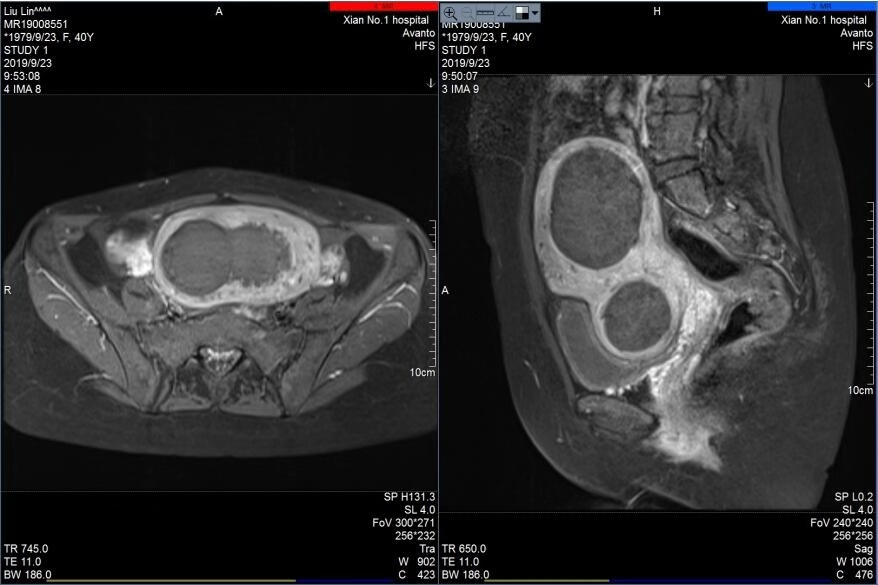

宋迎春主任在海扶刀治疗中心通过对其肌瘤进行上机定位与评估,患者完善了各项入院检查与胃肠道准备后,于2019年9月20日对其肌瘤进行海扶消融治疗,术中只用了752秒的辐照时间,就成功消融了7个肌瘤和1个腺肌瘤病灶,瘤体最大者近7cm,最小肌瘤约1cm,术前术后超声造影显示肌瘤大范围消融坏死,手术达到预期效果,患者十分满意。